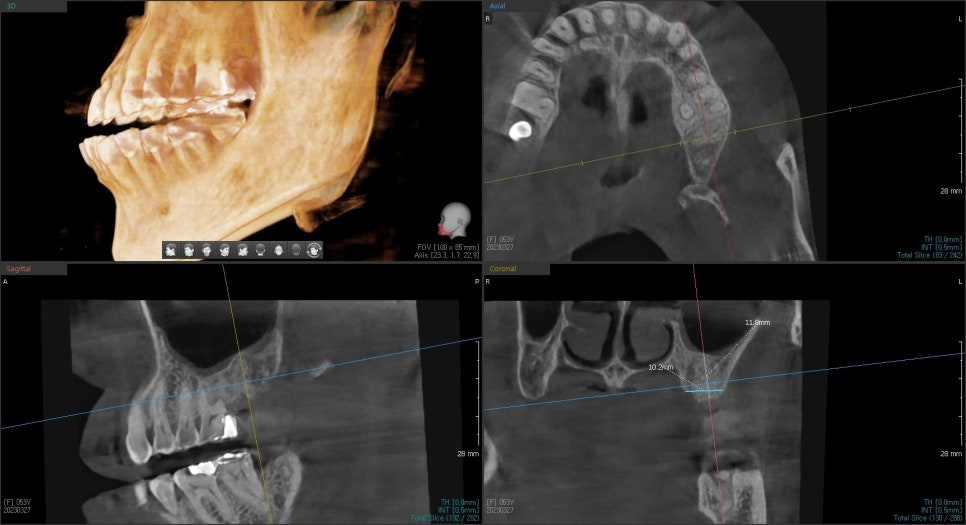

이 환자분은 4달 후 충분히 뼈가 형성이 된 후 임플란트 수술을 진행했습니다.

뼈의 형성도 좋았고 흡수도 많이 일어나지 않아

임플란트 식립 각도도 아주 유리하게 설정할 수 있었습니다.

임플란트 식립 후 주변 뼈와 고정이 일어날 때까지

기다렸다가 보철을 완성한 사진입니다.